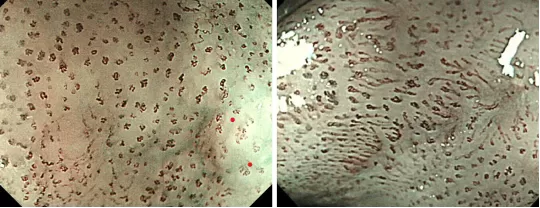

Ở thực quản, kỹ thuật nội soi phóng đại kết hợp ánh sáng dải tần hẹp giúp phát hiện và hạn chế bỏ sót các tổn thương phẳng, nhỏ hoặc mờ nhạt mà nội soi thông thường khó nhận diện. Đồng thời, phương pháp này cho phép quan sát rõ ràng các vòng mao mạch nội nhú (IPCLs) – một đặc điểm quan trọng trong chẩn đoán ung thư thực quản.

Hình ảnh: Các vòng mao mạch nội nhú trong tổn thương ung thư thực quản